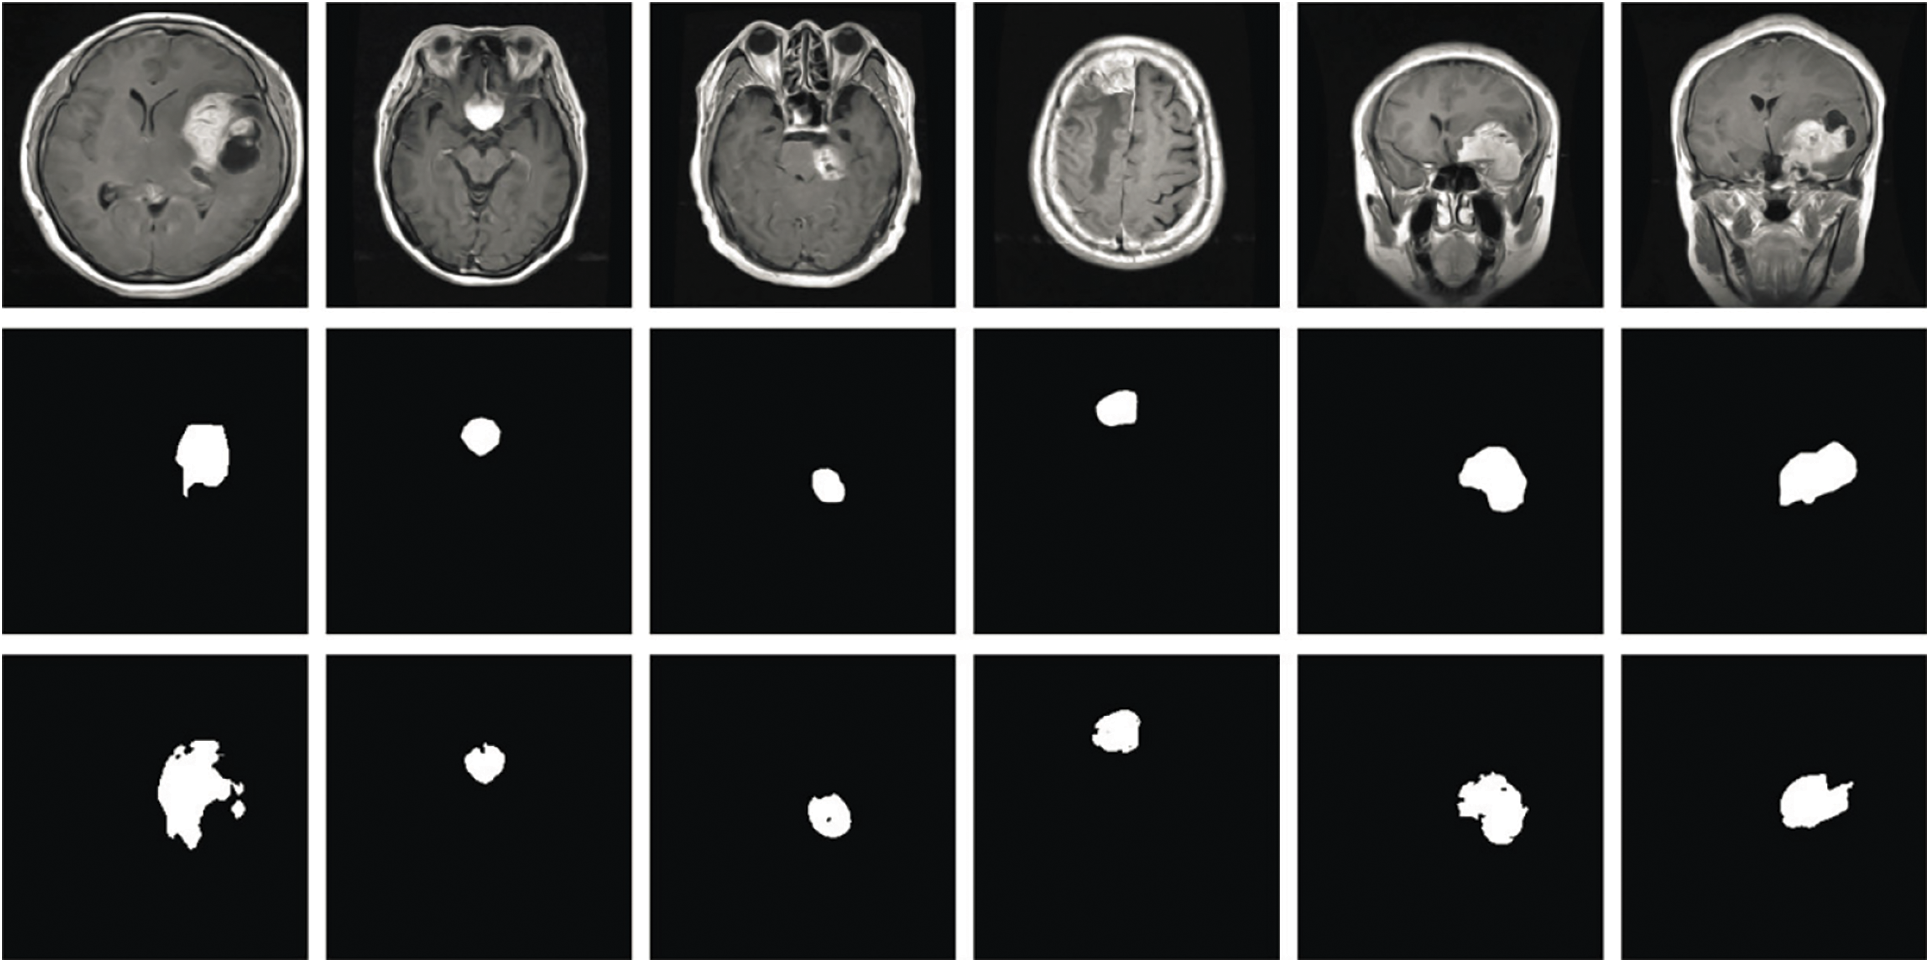

In Fig. 7, the clear visualization of tumor detection underscores the effectiveness of the brain tumor detection process.

Figure 7: Results of brain tumor segmentation using the proposed method. The initial row displays images from the database, the second row shows the ground truth, and the third row illustrates the algorithm-generated output